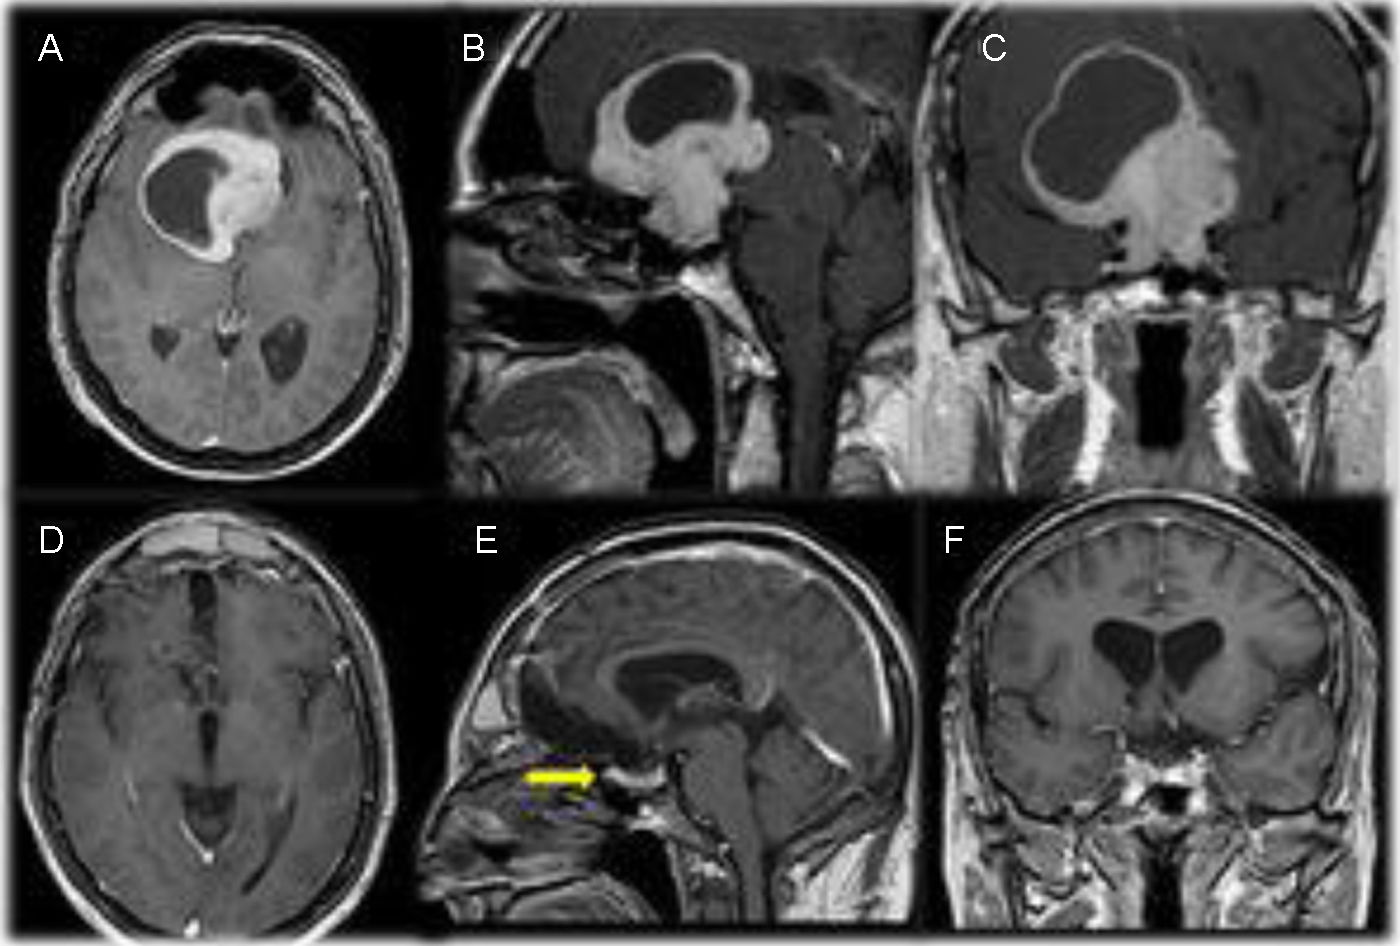

Material and methodsThis retrospective study analyzed 29 patients with giant pituitary adenomas (≥ 4cm) who underwent transcranial surgery between 2009 and 2018 at Bursa Uludağ University Faculty of Medicine. Inclusion criteria were: a minimum tumor diameter of 4cm, histologically confirmed pituitary adenoma, tumor resection via a transcranial approach, regular postoperative follow-up, and a minimum follow-up of 60 months. Data collected included patient demographics, clinical presentation, tumor characteristics, surgical details, extent of resection, and long-term outcomes (minimum 60 months follow-up).

ResultsThe mean patient age was 48.17±12.92 years. Vision loss was the most common presenting symptom (n=20). Gross total resection (GTR) was achieved in 51.7% (n=15) and subtotal resection (STR) in 48.3% (n=14). Postoperative improvement in visual function was observed in 48.3% (n=14), while 20.7% (n=6) experienced deterioration. Endocrinological remission occurred in 20.7% (n=6). Complications included diabetes insipidus (24.13%, n=7), cerebrovascular events (10.34%, n=3), and mortality (17.24%, n=5).